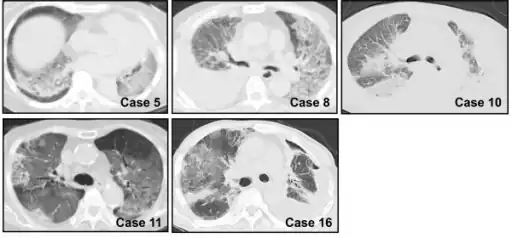

Chest CT images of five persons/cases who developed acute interstitial pneumonia

Acute interstitial pneumonia showing a marked reduction in lung capacity